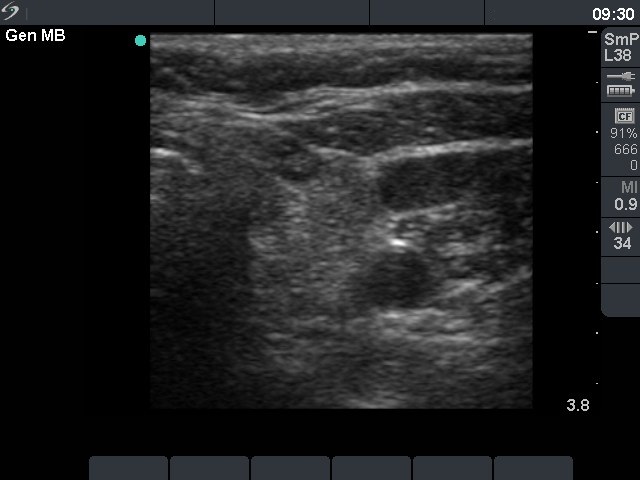

Chronic lymphocytic thyroiditis - Case 79. |

Clinical presentation: a 64-year-old woman was referred for an evaluation of clinical symptoms suggesting hyperthyroidism.

Palpation: no abnormality.

Hormonal investigation: indicated euthyroidism with TSH-level 2.98 mIU/L. Anti-TPO was elevated 306 U/mL.

Ultrasonography: there were small hypoechogenic areas in both lobes. The largest one contained hyperechogenic foci.

Cytology: lymphocytic thyroiditis.